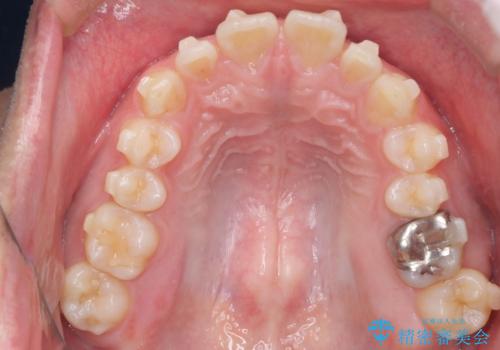

【前突症例】前歯を下げたい

- 前歯の隙間と口元を主訴に来院されました。

インビザラインにて治療を行いきれいな歯並びをつくることができました。

奥歯の噛み合わせもきちんと仕上げることができました。